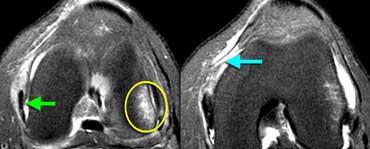

Viêm xương sụn bóc tách

Chẩn đoán Viêm xương sụn bóc tách thường được thực hiện trên X-quang.

Câu hỏi đặt ra khi chụp MRI là tổn thương ổn định hay không ổn định.

Ca lâm sàng bên trái là không ổn định vì hai lý do:

– Các nang nhỏ ở nền tổn thương (mũi tên đỏ)

– Quan trọng hơn là có dịch ở nền tổn thương (mũi tên xanh)

Lưu ý rằng lớp dịch này khác với AVN, nơi dịch nằm giữa sụn và xương.

Viêm xương sụn bóc tách không ổn định. Dấu hiệu duy nhất có giá trị để chẩn đoán OD không ổn định là dịch (mũi tên vàng), không phải phù tủy hay gián đoạn bề mặt xương sụn (mũi tên xanh lá).

Các dấu hiệu không có giá trị trong việc phân biệt OD ổn định và không ổn định bao gồm:

– Phù tủy xương (có thể gặp trong cả hai trường hợp)

– Gián đoạn bề mặt xương sụn.

Vì vậy, ca lâm sàng bên trái là không ổn định vì có dịch ở nền tổn thương.

Ca lâm sàng bên trái cho thấy viêm xương sụn bóc tách với phù tủy xương và gián đoạn bề mặt xương sụn.

Tuy nhiên, vì không có dịch, chúng ta không thể xác định đây là tổn thương ổn định hay không ổn định.

Trong phẫu thuật, tổn thương viêm xương sụn bóc tách được xác nhận là ổn định.

Trong những trường hợp không thể xác định tổn thương ổn định hay không ổn định, chụp MRI khớp có thuốc tương phản từ (MR-arthrogram) rất có giá trị.

Chúng ta tìm kiếm dấu hiệu Gadolinium thấm vào xung quanh tổn thương xương sụn.